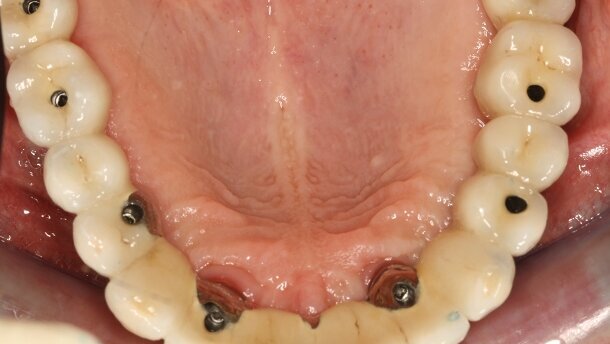

Implants pour ancrages d’une prothèse mandibulaire

Le facteur humain est essentiel lorsque nous considérons cette indication : ces patients sont âgés et possèdent souvent des ressources limitées. Une greffe osseuse ne fera donc jamais partie de notre plan de traitement, même si l’implant ne peut être placé dans une position académique. Il faut alors intégrer la notion de compromis, pour satisfaire au mieux la demande fonctionnelle et financière du patient. Dans la plupart des cas, les dents résiduelles dans le secteur antérieur sont extraites dans un premier temps, parce qu’elles interfèrent avec la pose des implants. Ces dents sont remplacées sur la prothèse existante, qui sera transformée en guide, en la perforant à l’endroit optimal où les implants devraient être positionnés. Le guide est utilisé à l’aveugle dans un premier temps avec le foret pilote. Par la suite, un lambeau est levé, permettant ainsi le meilleur positionnement dans l’os résiduel. Dans les cas où quelques dents sont dans un en état acceptable, il suffit de sélectionner une dent relativement indemne dans le secteur incisivo-canin, et la prendre comme guide pour le premier implant (Figs. 4 a et b). Il est essentiel de réaliser la prothèse définitive après que les implants aient été mis en fonction sur la prothèse initiale : cela permet au prothésiste de créer un volume de résine suffisant, et d’éviter les fractures intempestives par la suite.